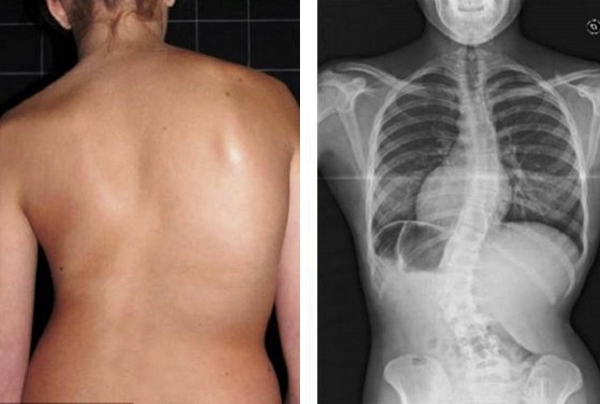

Lihat foto-foto ini. Inilah yang terjadi pada mereka yang tidak memperhatikan gejala. Hari ini, mereka adalah orang-orang yang tak berdaya, dan banyak di antara mereka tidak memiliki siapa pun untuk membantu. Apakah Anda menginginkan nasib seperti itu?

Wanita, 52 tahun. Pergeseran parah dan deformasi cakram tulang belakang dengan kompresi saraf serta kerusakan sumsum tulang belakang.

"Punggung bungkuk janda" — deformasi tulang belakang yang menyebabkan nyeri tak tertahankan yang semakin memburuk setiap hari.